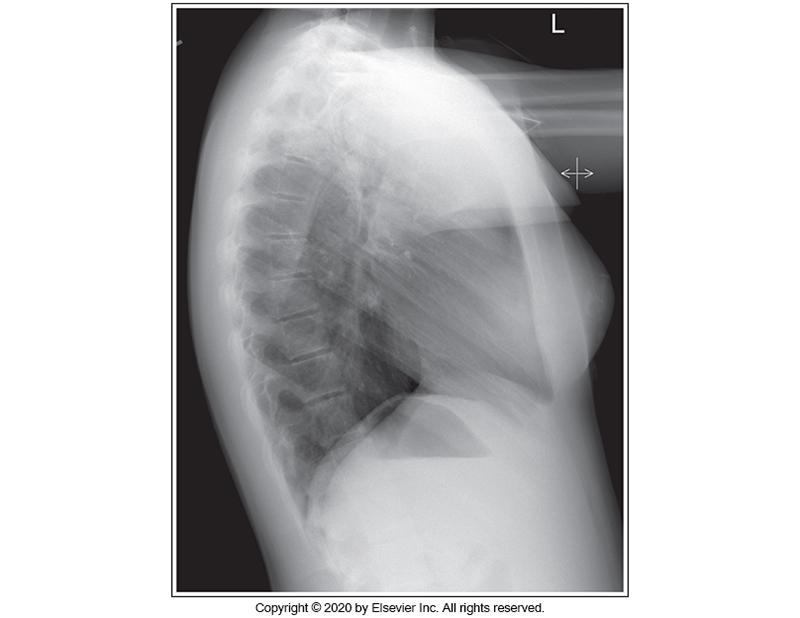

Identify the main problem of the image below (left lateral chest)

Tilt

Humeri not elevated.

CR angulation

Rotation